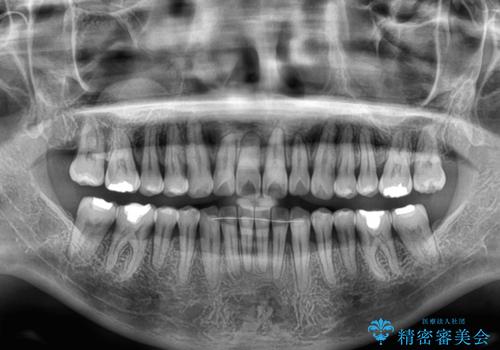

前歯のデコボコをインビザライン・モデレートで矯正治療

- 上下前歯のデコボコを気にして来院された患者様です。

安価なインビザラインパッケージを用いての治療を希望されており、デコボコの程度が中等度であったため、インビザライン・モデレートを用いて矯正治療を行うこととしました。

インビザライン・モデレートは、製作できるアライナーの枚数に制限があるため、移動可能な量に限りがあるものの、インビザライン・ライトよりも枚数が多いため、幅広い症例に対応可能です。